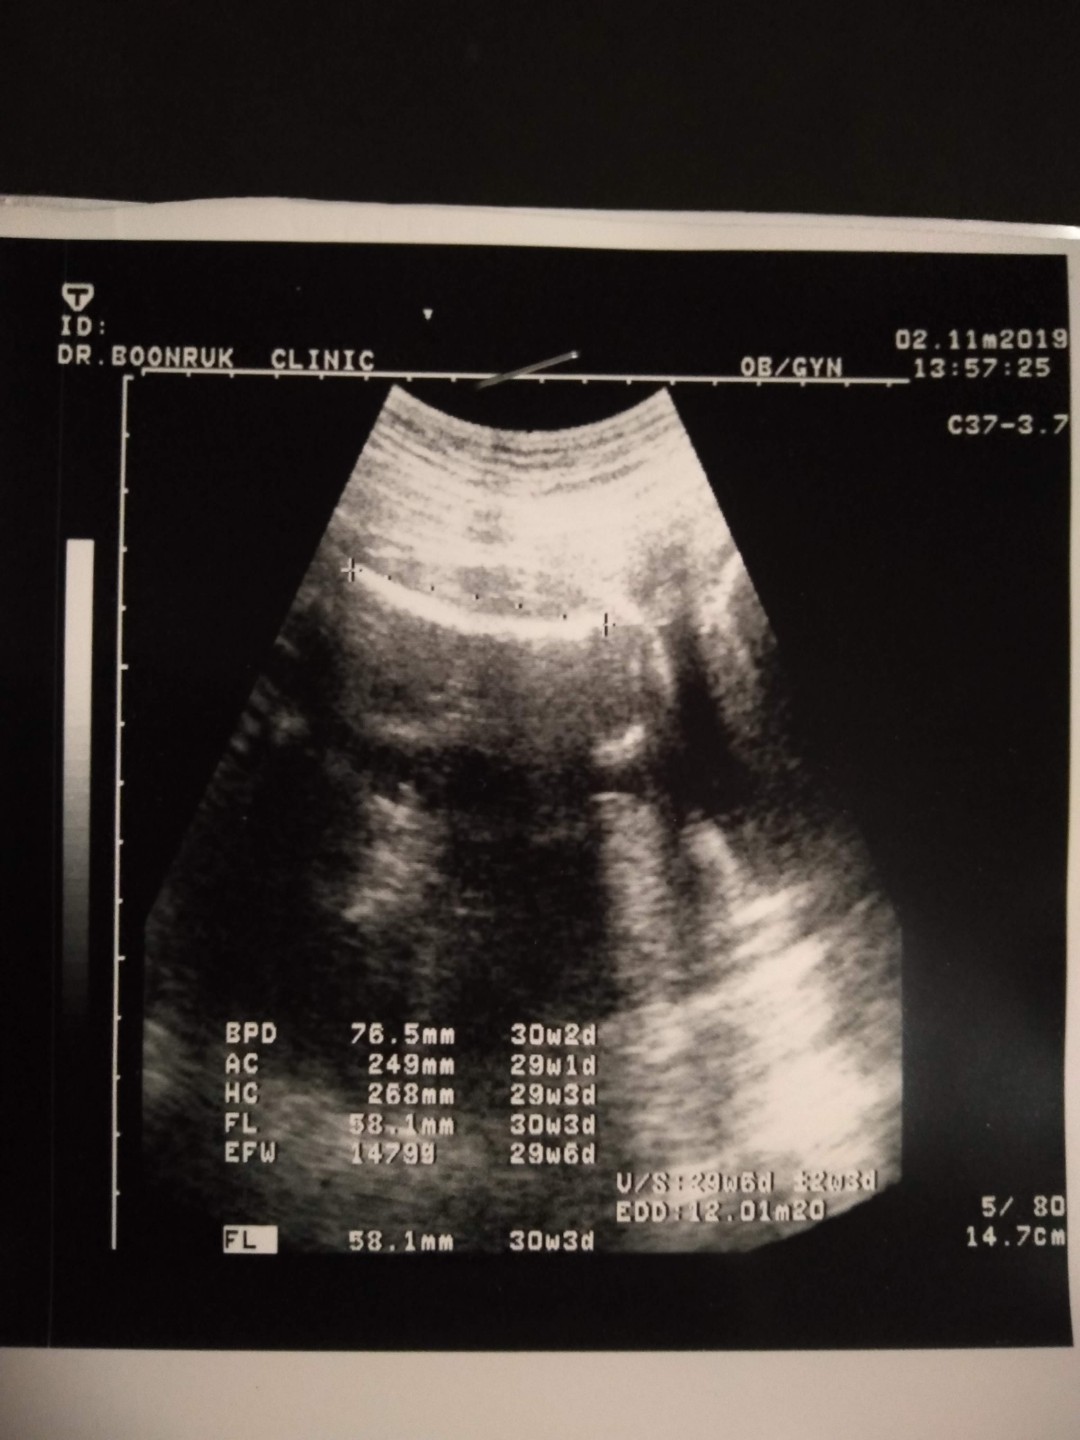

ตอน24wค่ะ